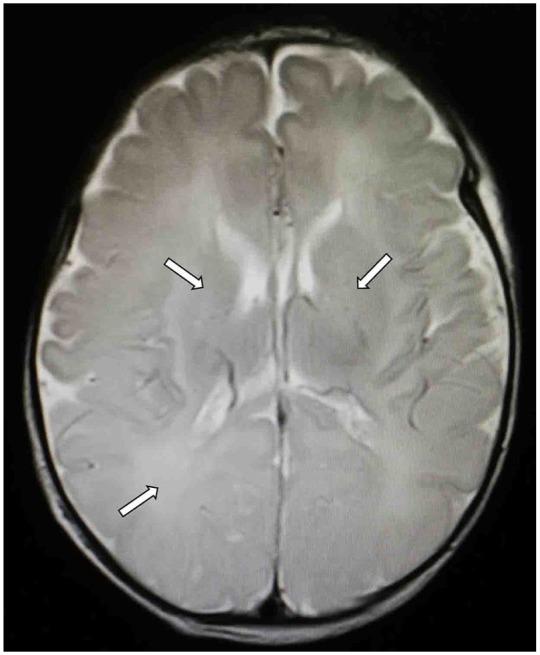

Magnetic resonance imaging showed evidences of abnormality in 54.54% (36 of 66) of hypoglycemic infants. The most common abnormal findings were located on the parietal and occipital lobes of the brains. The number of days with hypoglycemia was significantly higher for abnormal MRI infants ( < .001), and prolonged/recurrent hypoglycemia was remarkably distinguished for abnormal MRI infants ( < .001). Patients with abnormal MRI findings did not have a lower blood glucose than infants without abnormal MRI findings ( > .05), but the lowest blood glucose was significantly lower for the patients with seizures ( < .01).

CONCLUSIONS

The pattern of bilateral occipital cortical injury is the most common abnormality for neonatal hypoglycemia. The number of days with hypoglycemia, not the lower blood glucose, was significantly related to abnormal MRI infants.

磁共振成像显示54.54%(66例中的36例)低血糖婴儿有异常表现。最常见的异常发现位于大脑顶叶和枕叶。MRI异常婴儿的低血糖天数显著更多(<0.001),MRI异常婴儿的低血糖持续时间延长/反复低血糖情况也显著不同(<0.001)。MRI有异常发现的患者血糖并不比MRI无异常发现的婴儿低(>0.05),但癫痫患者的最低血糖显著更低(<0.01)。

结论

双侧枕叶皮质损伤模式是新生儿低血糖最常见的异常。低血糖天数而非更低的血糖水平与MRI异常婴儿显著相关。